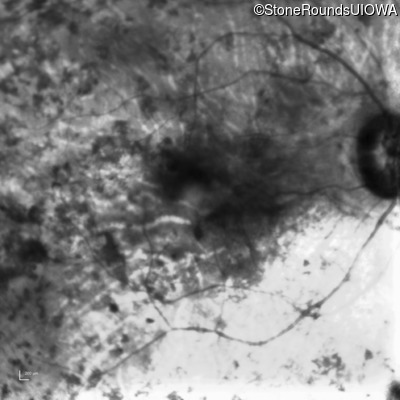

Type 1 Usher Syndrome (IB1a)

Age at visit: 62 years

This 62 year old man has had profound hearing loss since birth and has communicated using sign language for his entire life. He first noticed a problem with his vision at about age 11 when he noticed night blindness and began to trip over objects that he should have seen.